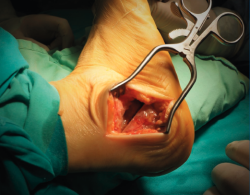

Introducción y objetivos: la enfermedad de Müller-Weiss (EMW) es una patología causada por la displasia del navicular que, en muchos casos, está mal o infradiagnosticada. Se presenta como un “pie plano-varo paradójico” y una artropatía talonavicular. En este trabajo pretendemos explicar nuestra experiencia con una cirugía de preservación articular –osteotomía “supervalguizante” de calcáneo aislada (de tipo Dwyer con desplazamiento lateral)– en nuestra primera serie de pacientes a los que no se realizó una artrodesis.

Introduction and objectives: Müller-Weiss disease (MWD), a tarsal navicular dysplasia, is often misdiagnosed or underdiagnosed. Clinical presentation as a paradoxical “flatfoot varus” combines with arthritic talonavicular changes. In the present study we show our experience with a joint-preserving surgical treatment –isolated “super-lateral-slide osteotomy”– in the first series of patients in which a tarsal arthrodesis was not performed.